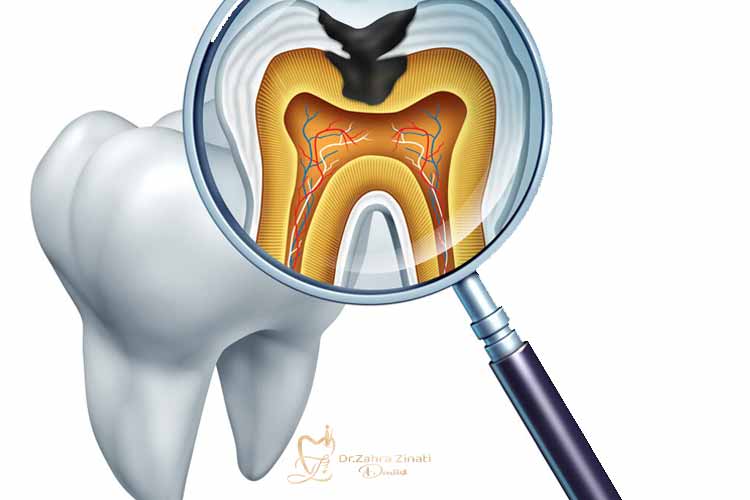

مینای دندان لایهای سخت و شفاف است که سطح خارجی دندانها را پوشانده و از آنها در برابر فشار جویدن، تغییرات دما و مواد شیمیایی محافظت میکند. با این حال، در اثر تماس طولانی با مواد اسیدی یا عوامل مکانیکی، این لایه دچار فرسایش میشود. فرسایش مینای دندان به مرور زمان شکل میگیرد و یکی از مشکلاتی است که میتواند بر ظاهر و عملکرد دندانها تاثیر بگذارد.

مینای دندان قابلیت ترمیم طبیعی ندارد و اگر آسیب ببیند، تنها راهکار موجود جلوگیری از پیشرفت فرسایش و انتخاب درمانهای دندانپزشکی مناسب است.

وقتی مینای دندان نازک میشود، لایه زیرین به نام عاج یا دنتین نمایان میگردد. این لایه رنگی زرد دارد و همین امر باعث تغییر رنگ کلی دندانها میشود. افرادی که به تغییر رنگ حساس هستند، ممکن است تصور کنند که تنها با سفید کردن دندان میتوانند این مشکل را حل کنند؛ اما در حقیقت، دلیل اصلی این زردی، ساییدگی مینا است و روشهای زیبایی بهتنهایی نمیتوانند مشکل را برطرف کنند.